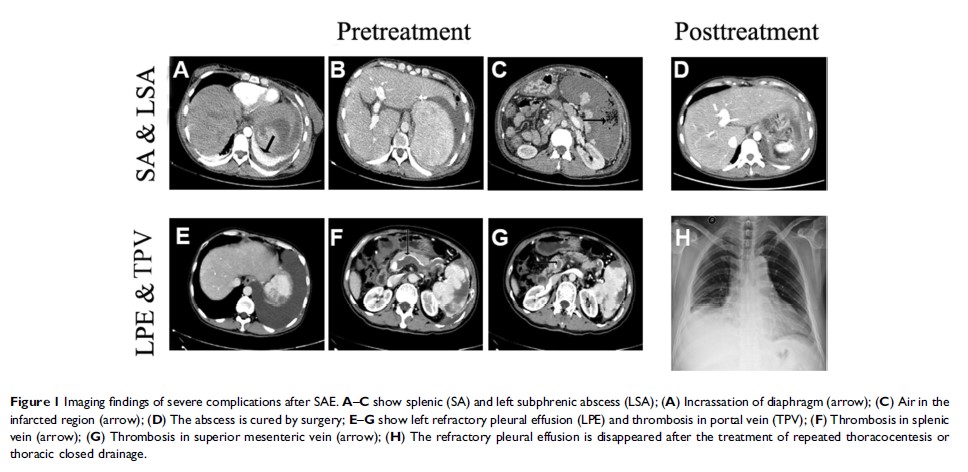

肝硬化门静脉高压病人脾动脉栓塞后严重并发症